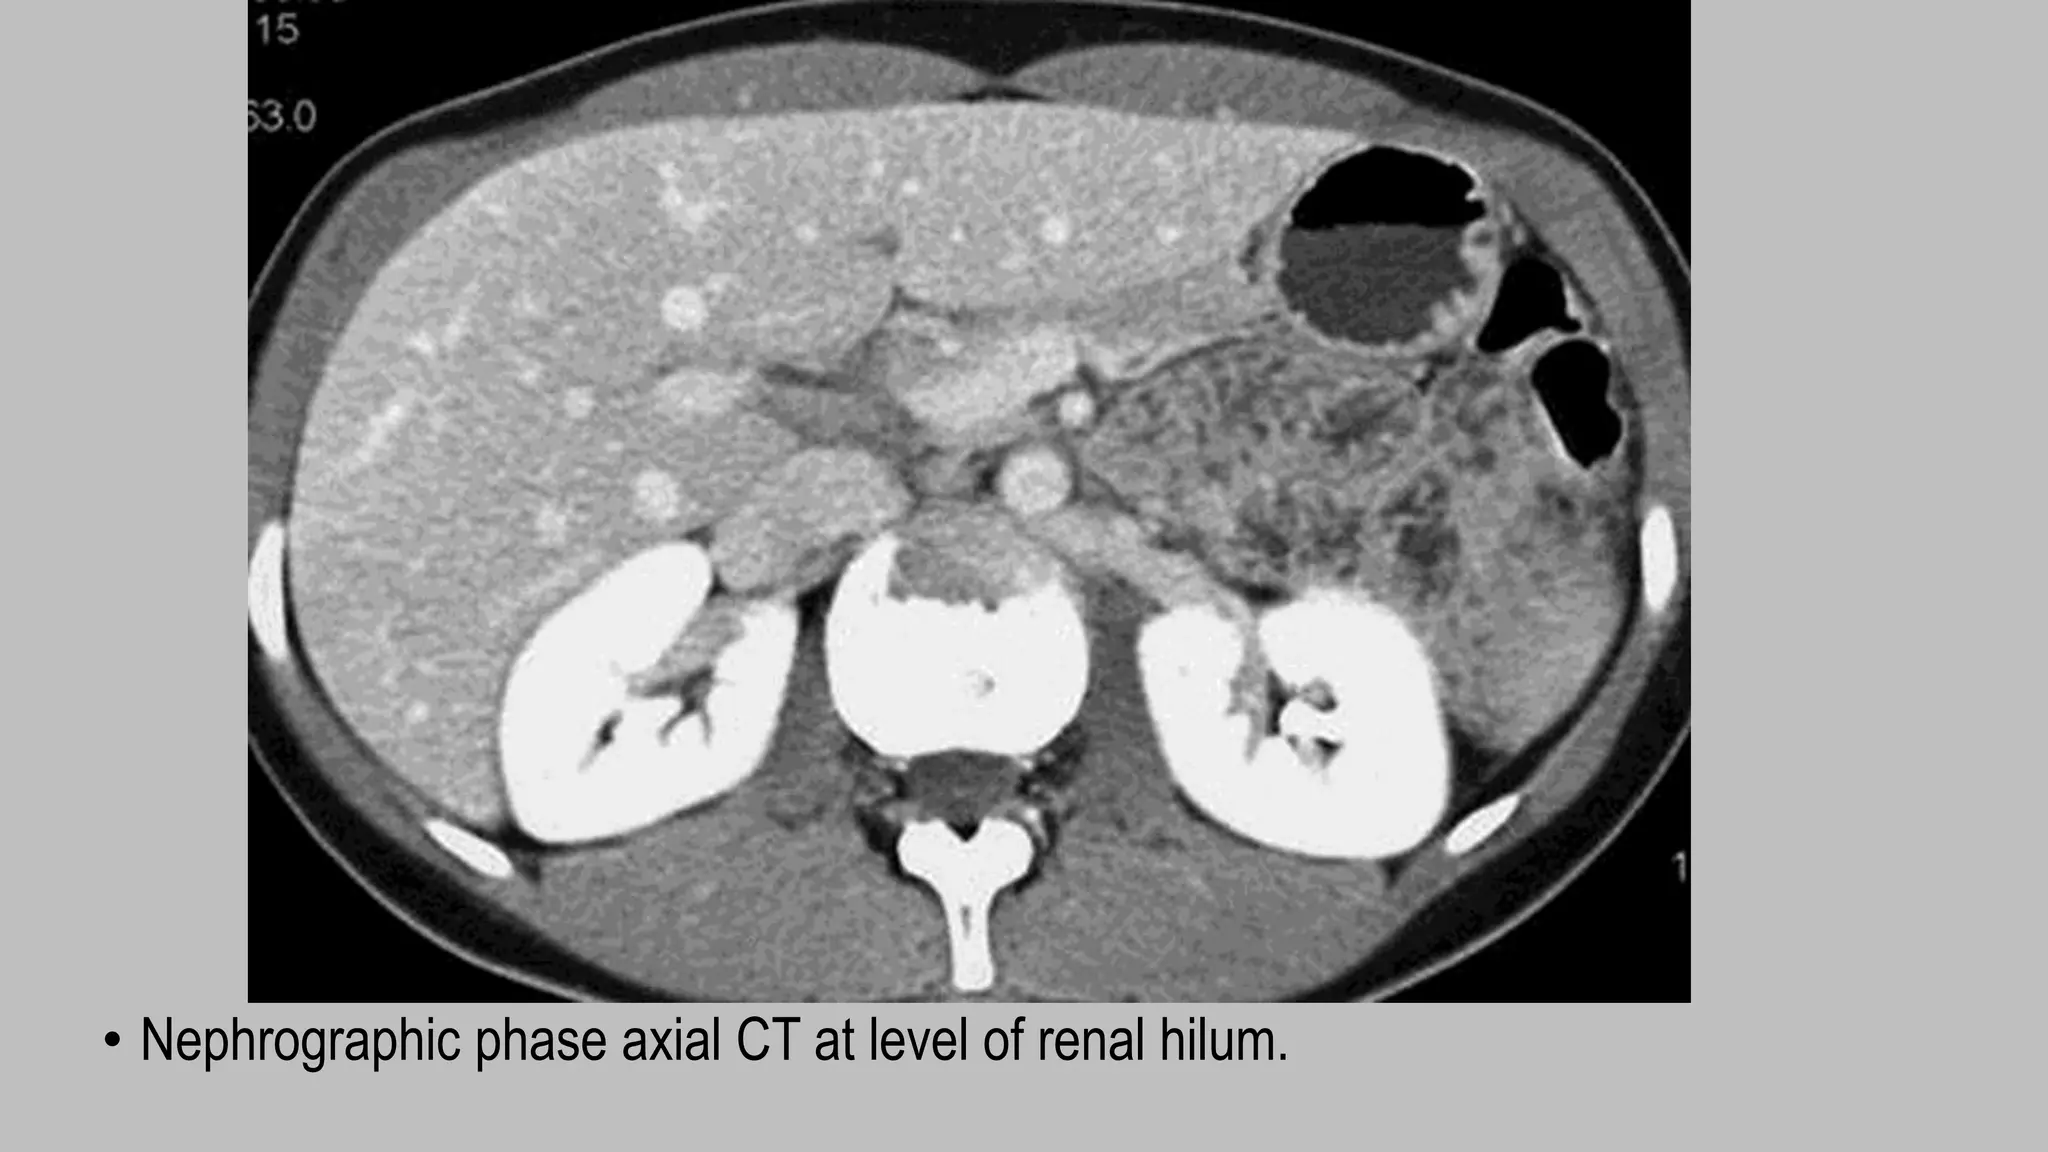

Nephrographic phase

• Nephrographic phase images are

acquired 90–100 seconds after

administration of a nonionic contrast

agent .

• Imaging (2.5- to 5-mm slice thickness) is

typically confined to the kidneys during

this phase.

• Nephrographic phase imaging has the

highest sensitivity in the detection of

renal masses, and correlation with

unenhanced images is required to show

unequivocal enhancement.

• Nephrographic phase axial CT at level of renal hilum.